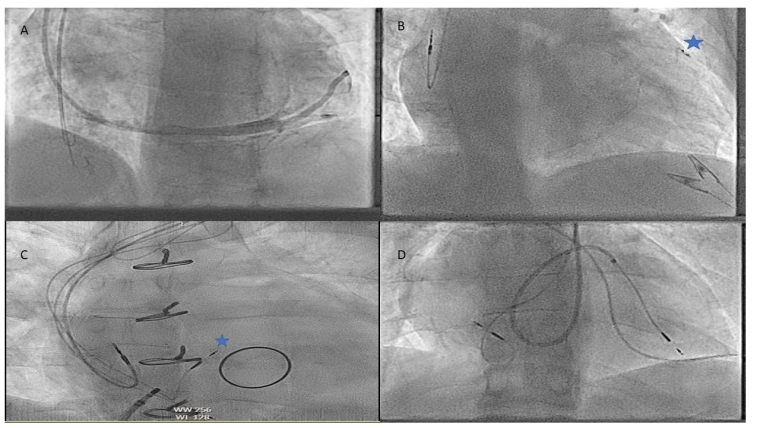

Next in periprocedural preparation is to plan how to deliver the lead or leadless device which may require an understanding of obstructions such as baffles, conduits and valve replacements which are more relevant as the complexity of CHD rises. In addition to just delivering a lead to a location there can be issues as to whether the area the cardiologist can reach is paceable, such as in the Fontan circulation [7].

7. Atrial switch procedure with baffles preventing easy sheath delivery to the septum.

Again, ventricular pacing here is to a subpulmonary left ventricle and the angulation via the atrial baffle can be difficult with a lead that will bias to the left ventricle (LV) free wall or left atrial free wall. Delivery of the atrial lead almost always requires an active lead and position, again, can be difficult as the baffle may direct the lead towards the ventricle. Care must be taken also to test and ensure no phrenic capture due to the position of the leads in the LV and left atrium.

Prior to pacing in this cohort, an assessment should be made to ensure there is no baffle stenosis in the SVC baffle before the leads are placed, as prestenting a stenosis is recommended.